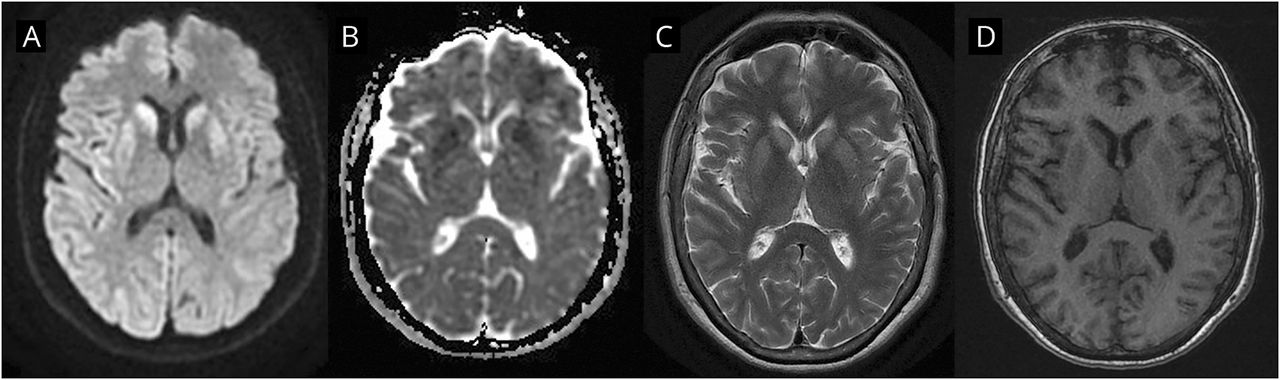

图2

核磁共振成像发现克雅二氏症的皮层和纹状体扩散限制

轴向部分(A) diffusion-weighted成像,(B)表观扩散系数,(C) T2加权,和(D) T1加权磁共振成像序列显示真正的扩散限制两国尾状核和壳核和多个脑回,更在右边(皮质过程),但没有其他变化在T2和T1。